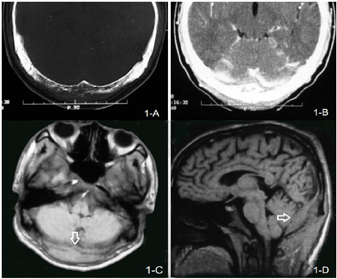

血、尿常规、肝、肾功能正常,便潜血(+);HbsAg(+),HbcAb(+),HIV抗体(-),血沉、自身抗体、肿瘤标志物未见异常,血清免疫固定电泳、血、尿轻链定量正常,尿本-周氏蛋白(-),血β2微球蛋白4.8μg/ml(正常值1.5~2.7 μg/ml)。胸X线及腹部超声未见异常。血涂片、骨髓涂片及活检正常。头CT示枕骨骨质破坏,增强后枕部硬脑膜与小脑幕强化,MRI可见枕部硬脑膜增厚(图1)。头和全身骨显像示枕骨左侧异常放射性浓聚区。

腰椎穿刺:压力235 mmH2O,脑脊液细胞总数2×106/L,蛋白0.4 g/L,糖和氯化物正常,墨汁染色、抗酸染色、细菌、结核菌涂片及培养等阴性。脑脊液细胞学检查:可见大量大幼稚淋巴样细胞,呈类圆形,直径15~20μm,胞浆嗜碱、稀少,围绕细胞核呈花变样分布,部分可见核旁胞质空晕,核大而饱满,类圆形、畸形,可见双核,染色质丰富,细颗粒状,分布均匀,(相对正常淋巴细胞)较疏松,嗜碱性核仁明显;偶可见正常淋巴细胞;免疫细胞学染色:CD34(+),CD20(-);脑脊液细胞学提示恶性淋巴瘤(图2)。随即转入神经外科行枕部探查活检及寰枕减压术。